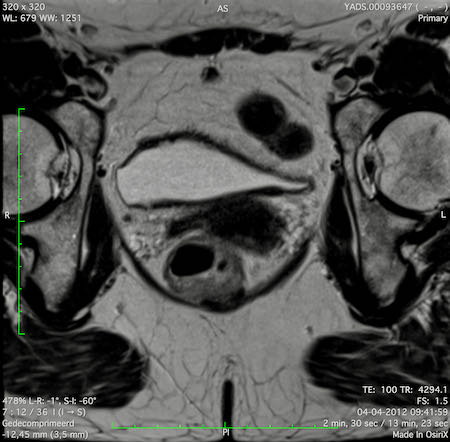

Hình ảnh

Các hình ảnh được cung cấp cho thấy ung thư biểu mô tế bào nhẫn với tình trạng dày lan tỏa thành trực tràng, hình ảnh bia bắn điển hình, và sự xâm lấn mỡ mạc treo trực tràng.